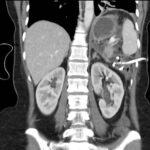

Mujer de 36 años que ingresa a Hospital Sanatorio Franchin el 11 de octubre de 2023 de forma programada para realización de duodeno pancreatectomía cefálica por tumor de cabeza de páncreas en estudio. Refiere hallazgo de lesión en forma incidental durante estudio de control hace dos meses por presentar antecedentes familiares (neoplasia endocrina múltiple). Se interna para manejo quirúrgico. Estudios de tomografía revelan formación nodular localizada en cabeza y cuerpo pancreático de paredes gruesas que mide 24 x 28 mm, que en resonancia se muestra hiperintensa en T2 y realce periférico luego de la administración de contraste endovenoso. Presenta restricción en la difusión con caída de la señal ADC, por lo que se vincula con una lesión de alta celularidad.

Ahora bien, como se mencionaba al principio, el estudio ecográfico es de muy baja sensibilidad y se identifique o no la lesión por este estudio, nuestro siguiente paso en el algoritmo diagnóstico de esta lesión es la tomografía. Esta es la prueba no invasiva inicial, con una sensibilidad del 63% al 83%, y detecta del 70% al 80% de los tumores. Esta debe realizarse como un estudio trifásico: fase arterial temprana a los 30 segundos, fase venosa a los 70 segundos, fase tardía de 3 a 5 minutos. La característica de estos tumores por tomografía es que se presentan como una masa sólida que tiene un ávido realce en la fase arterial, cuyo realce se mantiene y se observa más tenue en la fase venosa y en los tiempos tardíos la lesión se homogeniza.

Para mi caso, y dando una visión general de los métodos de imagen no invasivos en esta revisión retrospectiva, solo a uno de los pacientes se le detectó la lesión por ecografía, donde se visualizó una lesión nodular hipoecogénica en el cuerpo del páncreas. A los demás pacientes se les detectó la lesión por tomografía en estudio trifásico, donde resaltan las características ya descritas por la literatura de lesiones hipervasculares con intenso realce en fase arterial, localizadas en diferentes partes del páncreas, como cabeza, cuerpo y cola.

La resonancia magnética confirmó aún más el diagnóstico de las lesiones ya previamente visualizadas en tomografía en esta revisión, con realce de las lesiones en secuencias T1 y contraste con gadolinio, y en las secuencias funcionales con restricción de la lesión y caída de la señal en el mapa de ADC.